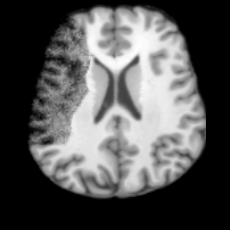

(a)PathologicalInput ImageSynthSR [18]Brain-ID [28]UNA [30]USBHealthyGround TruthRefer to captionRefer to captionRefer to captionRefer to captionRefer to captionRefer to captionRefer to captionRefer to captionRefer to captionRefer to captionRefer to captionRefer to captionRefer to captionRefer to captionRefer to captionRefer to captionRefer to captionRefer to captionRefer to captionRefer to captionRefer to captionRefer to captionRefer to captionRefer to caption(b)HealthyInput ImageConditionalLesion MaskUNA [30]USBRefer to captionRefer to captionRefer to captionRefer to captionRefer to captionRefer to captionRefer to captionRefer to captionRefer to captionRefer to captionRefer to captionRefer to captionRefer to captionRefer to captionRefer to captionRefer to caption

Figure 5: Comparison of bidirectional brain editing. (a) pathology-to-healthy, the circles and arrows highlight lesion regions and unsuccessful reconstructions; (b) healthy-to-pathology. Note that SynthSR and Brain-ID cannot perform healthy-to-pathology editing.

Healthy-to-Pathology Editing. As shown in Fig. 5 (b), given a healthy brain image paired with a random lesion mask, USB seamlessly embeds the lesion into the healthy anatomy, producing realistic pathological appearances consistent with surrounding structural context. Yet UNA’s syntheses are visually unrealistic, with the conditioned lesion mask simply overlaid as a parallel layer onto the healthy brain. Tab. 3 further demonstrates USB’s superior performance. The evaluation was conducted on 100 pairs of lesion masks and healthy brains, with real stroke images